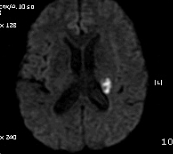

PCA terrotory infartion + AchA territory

B MRI 촬영 결과는 좌측의 corona radiata, Lt temporo-occipital lobe 의 subcortical area 의 optic radiation 부위를 비롯한 여러 군데 점상 병변. N/S 정주하고 Aspirin 투여 시작, 혈압약은 지속 투여, SBP 160정도로 유지.

촬영 결과는 좌측의 corona radiata, Lt temporal lobe는 anterior choroidal artery 영역입니다.

사진에는  left PCA distal 이후가 보이지 않습니다. (맞나요..?)

좌측사진은 PCA 영역. 우측사진은  AchA 영역의 post. periventricular corona radiata (Stroke 4ed p199, Fig 9-3 과 동일)

DWI coronal or saggital view 보면 분명하겠지만 이 사진으로 보니 PCA territory infarction으로 모두 설명되는 것 같습니다. PCA 영역에 hypoperfusion으로 병변이 크지는 것 같습니다. 5-7일 지나야 안정기에 들어갈 것 같습니다.